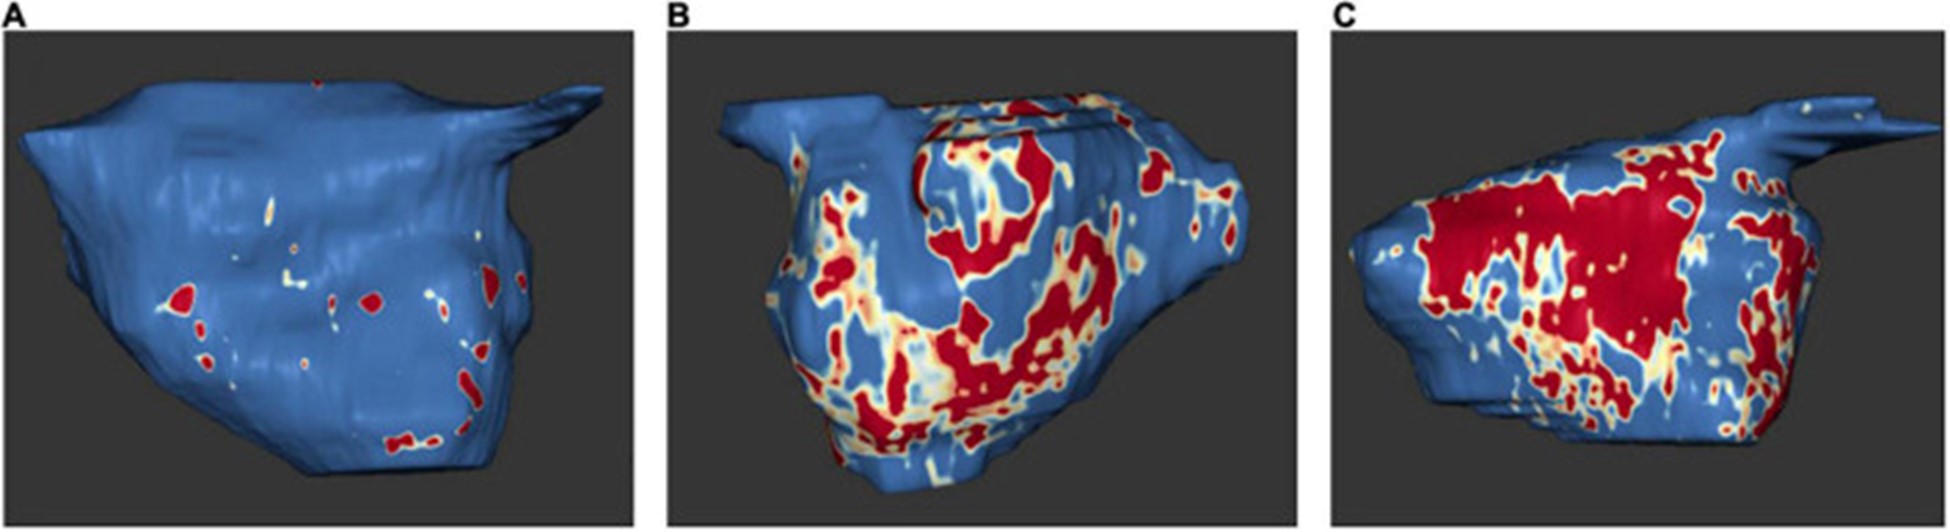

2009 年,Oakes 等人。建立了犹他阶段模型来量化 LA 纤维化 。根据该模型,将严重程度分为四个级别:犹他州 I,定义为 ≤ 5% LA 壁增强,犹他州 II,5–20%,犹他州 III,20–35%,犹他州 IV,>35% (图 5)。

图 5:左心房 MRI 检查示例:基于 3D 延迟增强磁共振成像扫描的左心房组织纤维化。正常左心房壁以蓝色显示,纤维化改变以红色和白色显示。纤维化量占左心房壁总体积的百分比。(A)犹他州第一阶段 (1%)。(B)犹他州第 3 阶段 (27%)。(C)犹他州第 4 阶段 (36%)。在 Misagh Piran 博士(Herz- und Diabeteszentrum Nordrhein-Westfalen,Ruhr-Universität Bochum)的友好支持下。

延迟增强 MRI 与来自 LA 结构重塑的手术活检组织学之间发现了高度相关性,包括间质和脂肪纤维化以及总纤维化和脂肪 。原生 T1 对应于 MRI 和组织学的纤维化程度 。此外,与没有 AF 的患者相比,AF 患者的 LA 壁增强似乎更大(77)。

延迟增强 MRI 发现的 LA 瘢痕区域与心内膜标测中的低电压区域有关 。

由于 LA 晚期钆增强与 LA 射血分数和超声心动图左室间隔 e' 和室间隔 E/e' 之间存在显着相关性,因此更高量的 LA 晚期钆增强与 LA 功能下降以及 LV 舒张功能下降有关(79)。斑点追踪超声心动图也证明了延迟增强和 LA 功能降低之间的相关性。延迟增强 MRI 测量的 LA 壁纤维化程度与斑点追踪超声心动图显示的 LA 应变和应变率之间存在反比效应,特别是 LA 中外侧应变和应变率(80)。有趣的是,与阵发性 AF 患者相比,持续性 AF 患者出现更多的纤维化和更少的中间隔和中外侧应变 。一般来说,新发房性心律失常的风险随着 LA 晚期钆增强量的增加而增加 。

既往卒中患者和卒中高危患者(表现为 CHA2DS2-VASc 评分高)在延迟增强 MRI 中 LA 纤维化的比例显着增加。LA 纤维化是脑血管事件的独立预测因子,显着提高了 CHA2DS2-VASc 评分的预测能力 。上升的犹他阶段和更强烈的 LA 晚期钆增强与主要心血管事件的风险增加有关,主要是由于中风或 TIA 的风险增加(82)。有趣的是,与 AF 患者相比,ESUS 患者的心房纤维化程度相似,这支持了纤维化是缺血性卒中和左心房心肌病的主要危险因素的假设(83)。

通过延迟增强 MRI 测量的结构性 LA 重塑程度似乎与 AF 类型(孤立性 AF 或非孤立性 AF)无关(84)。已证明 AF 消融后的结果显着取决于结构性 LA 重塑的程度,在犹他州分期增加时结果更差 。随着延迟增强水平的增加,消融后 AF 复发的发生频率更高(75)。因此,通过延迟增强 MRI 进行的消融前 LA 纤维化评估可以预测结果 。另一项研究 LA 纤维化对 AF 消融后结果的影响的研究表明,延迟增强 MRI 检测到的 LA 纤维化等级较高时,复发性心律失常的风险出现。77 )。较高的 LA 纤维化等级的存在也是成功消融的最佳预测指标,而增加的 LA 体积和持续性 AF 没有预测作用 。